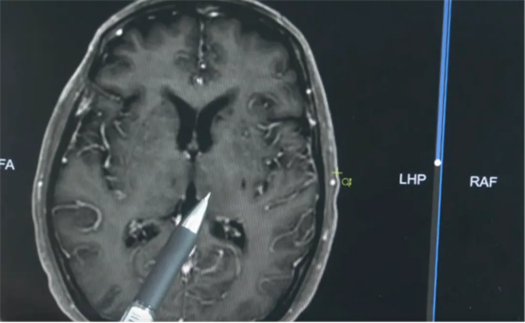

医生解释说:“正常的大脑,血脉屏障是完整的,造影剂没办法通过。但当脑子出现炎症,血脑屏障的通透性就会增加,白色的造影剂就会渗入脑子,这就提示我们脑子有炎症表现。”正是这种猪链球菌脑膜炎,影响了明叔大脑的听力区。